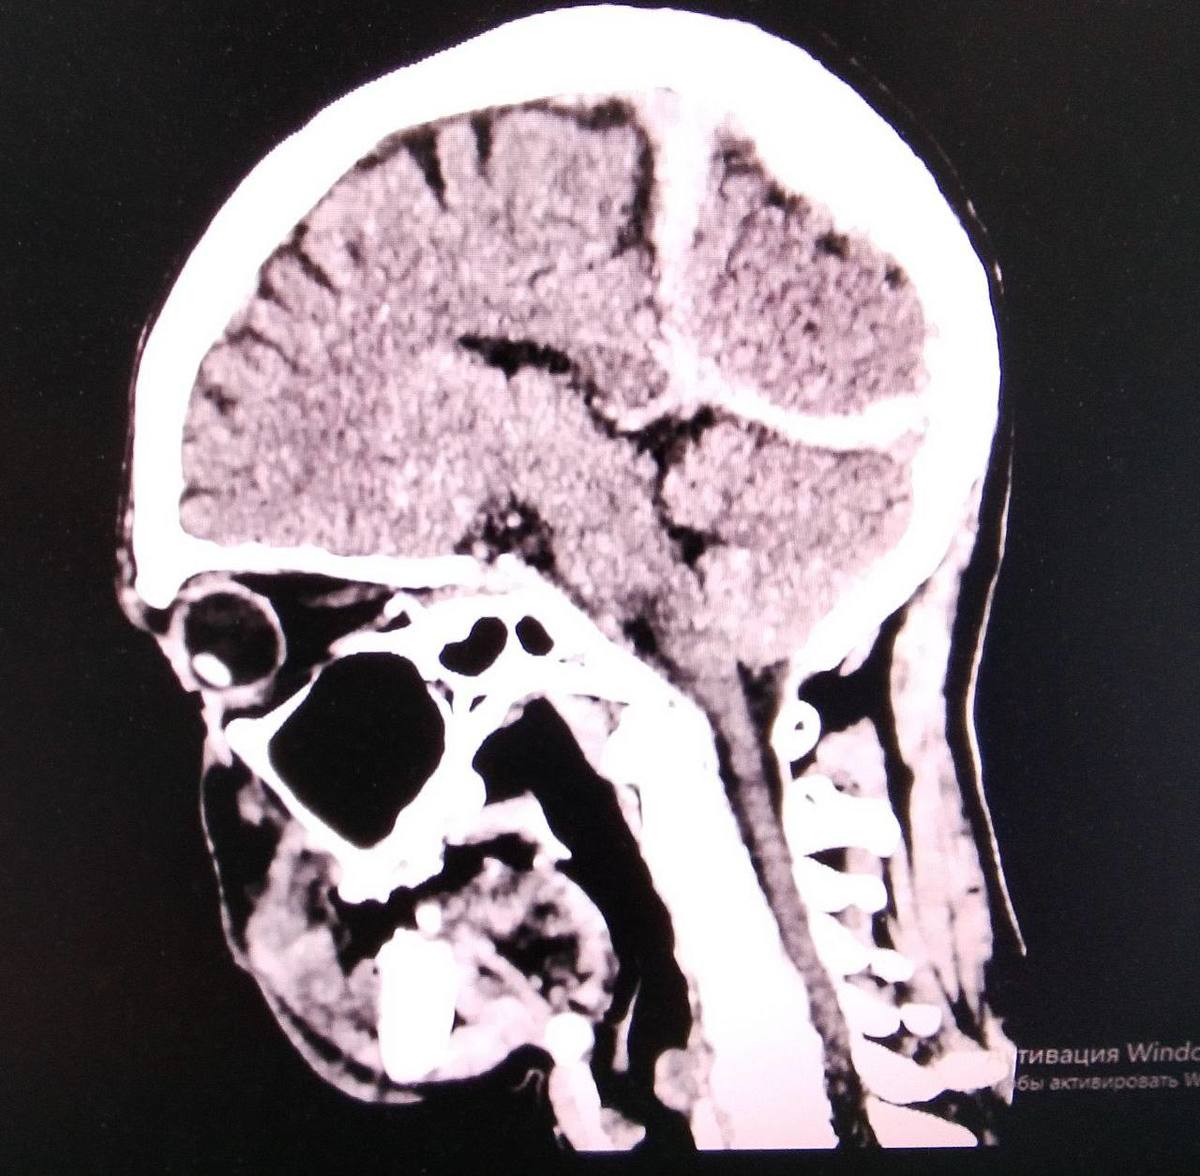

В январе житель Спасска-Дальнего получил тяжёлые травмы после падения на скользкой дороге. Он был одет не по погоде, потерял сознание и около трёх часов находился на морозе, что привело к общему переохлаждению. Пострадавшего обнаружили местные жители, после чего он был экстренно доставлен в Спасскую городскую больницу.